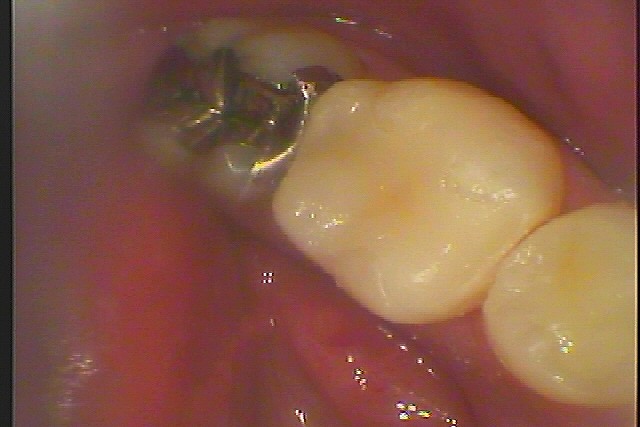

左下6番のアマルガムを外して虫歯治療 昔の銀歯でもアマルガムは水銀や体内に入っては有毒な金属で作られていました 40代男性 |お知らせ |広島市安佐南区の歯科医院 左下6番のアマルガムを外して虫歯治療 昔の銀歯でもアマルガムは水銀や体内に入っては有毒な金属で作られていました 40代男性 トップ お知らせ・ブログ お知らせ 左下6番のアマルガムを外して虫歯治療 昔の銀歯でもアマルガムは水銀や体内に入っては有毒な金属で作られていました 40代男性 左下6番のアマルガムを外して虫歯治療 昔の銀歯でもアマルガムは水銀や体内に入っては有毒な金属で作られていました 40代男性 この銀歯を外していきます 左下6番の虫歯治療 銀歯を外したところになります 虫歯を除去していきます CR樹脂にて覆罩を行っていきます セレックセラミックにて審美修復を行っていきました Web診療予約 初めての方へ 選ばれ続ける理由 院内設備について 歯が痛いしみる一般歯科 歯がぐらぐらする歯周病 健康な歯を保ちたい予防歯科 子供の虫歯予防をしたい小児歯科 銀歯をセラミックに審美歯科 白い歯を目指しませんか?ホワイトニング 矯正専門医がいるので安心矯正歯科 抜けた歯を補いたいインプラント・入れ歯 医院案内 スタッフ紹介 メリィハウス歯科クリニックオフィシャルホームページ ラベンダー歯科クリニックオフィシャルホームページ お知らせ・ブログ ホーム 診療科目 一般歯科 歯周病治療 予防治療 小児歯科 審美治療 ホワイトニング 矯正歯科 入れ歯・インプラント マウスピース矯正 初めての方へ 院長・スタッフ 設備紹介 医院案内・アクセス メニューを閉じる